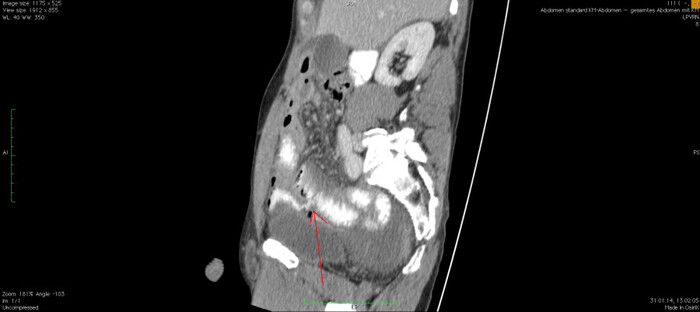

Мужчина, 32 года. Во время игры в футбол получил удар в низ живота, игру продолжил. Впоследствии боли в животе усиливались, стали нестерпимыми, ухудшилось общее самочувствие. На следующий день после игры пошёл сдаваться в больницу. Хирурги клинически описывают разлитой перитонит (воспаление брюшины) и отсылают пациента к нам на КТ, которое мы провели с внутривенной дачей контраста + заставили контраст ещё выпить (специальный раствор для перорального применения).

Так как клиника у нас острого живота после тупой травмы, учитывая что боли во всём животе и признаков большой кровопотери нет, то первое, что ищем - это свободный газ в брюшной полости, и находим его! (для этого лучше всего подходит т.н. лёгочное окно, как представлено ниже, или можно искать в костном окне - это спец.настройки яркости и контраста для просмотра разных структур тела - лёгкие, мозг, мягкие ткани, кости):

Итак, имеет место быть свободный газ в брюшной полости + свободная жидкость + перитонит. Определённо перфорация! Осталось найти источник. Желудок не подходит по механизму, а точнее по локализации травмы. Мочевой пузырь - в нём нет воздуха. Остаётся методом исключения только кишечник. Толстый или тонкий? Явно не верхние отделы толстого кишечника (ободочная кишка в области печеночного и селезеночного углов, а также поперечная исключаются - было бы больше воздуха). Сигма и нисходящая тоже заполнены стулом и воздухом. Получается, что тонкий кишечник всему виной.

Верхние (проксимальные) отделы точно не причём. Жидкость (звёздочки) больше в малом тазу, тут же и воздух. Для сравнения верхний этаж:

Hижний этаж:

И тут СТОП! А это чтo такое???

Кишке это точно не принадлежит, как ни крути. Это вышедший за пределы кишки контраст, который пациент выпил!

Осталось только место выхода найти:

Итого: перфорация тощей кишки в дистальных отделах, разлитой перитонит.

Был успешно прооперирован, место перфорации ушито, выписан.